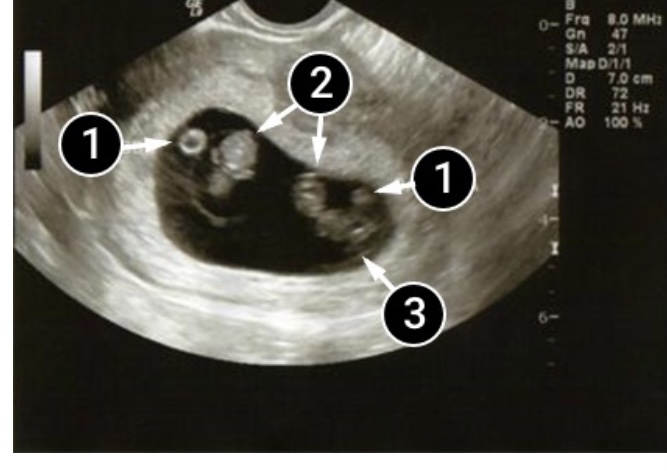

La siguiente foto muestra gemelos. En este caso, el septo amniótico está ausente.

Un bebé está claramente visible en la esquina superior izquierda. Un círculo claro y brillante a la izquierda de la cabeza es su saco vitelino personal. Los pequeños brazos están doblados a nivel de los codos.

Uno de los bebés está girado para mirar a su hermanito. En la parte inferior de su cuerpo, el punto redondo negro que ves es su vejiga. El círculo justo encima de él y a la derecha es su propio saco vitelino. Podemos ver La capa endometrial alrededor del saco amniótico común.

- Sacos vitelinos.

- dos embriones

- endometrio